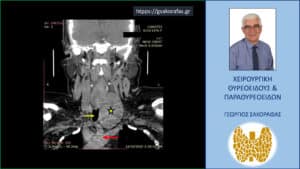

Αξονική τομογραφία – εγκάρσια διατομή στο ύψος του τραχήλου. Ο ευμεγέθης όζος (κίτρινος αστερίσκος) που απωθεί την τραχεία προς τα αριστερά (κίτρινο βέλος).